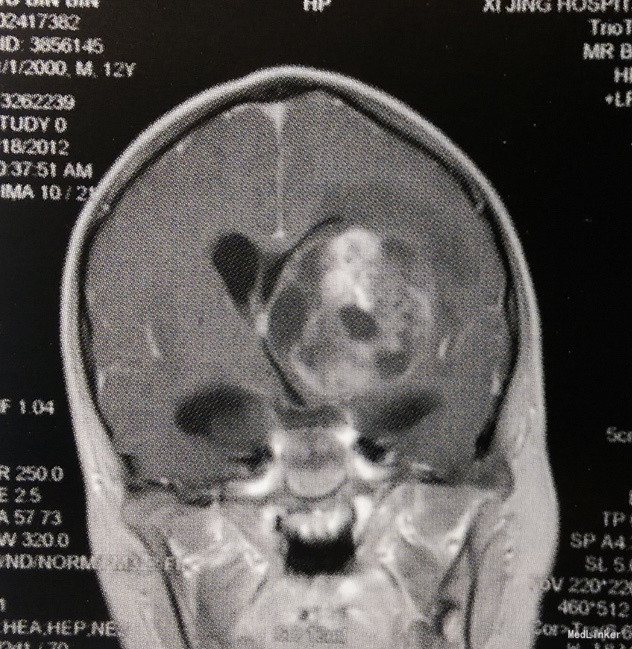

体格检查:意识呈昏睡状,查体不配合,双侧瞳孔等大等圆、对光反射迟钝,四肢肌力III级,肌张力轻度增高,右侧Babinski征阳性,颈抵抗阳性。 头颅MRI检查:左侧基底节区及丘脑占位性病变,呈囊实性混杂成分,边界欠清,实性成分呈明显不均匀强化,考虑生殖细胞瘤或胶质瘤可能性大;左侧侧脑室明显受压变形,中线向右侧移位;幕上梗阻性脑积水。